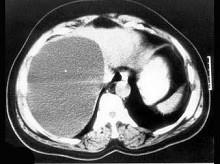

问题 对无并发症的先天性肝囊肿的治疗,正确的是 ( )

选项 A、经腹腔镜囊肿“开窗术” B、囊肿切除术 C、剖腹囊肿“去顶术” D、囊肿空肠Y形吻合术 E、B超引导下囊肿穿刺抽液术

答案 ABCE